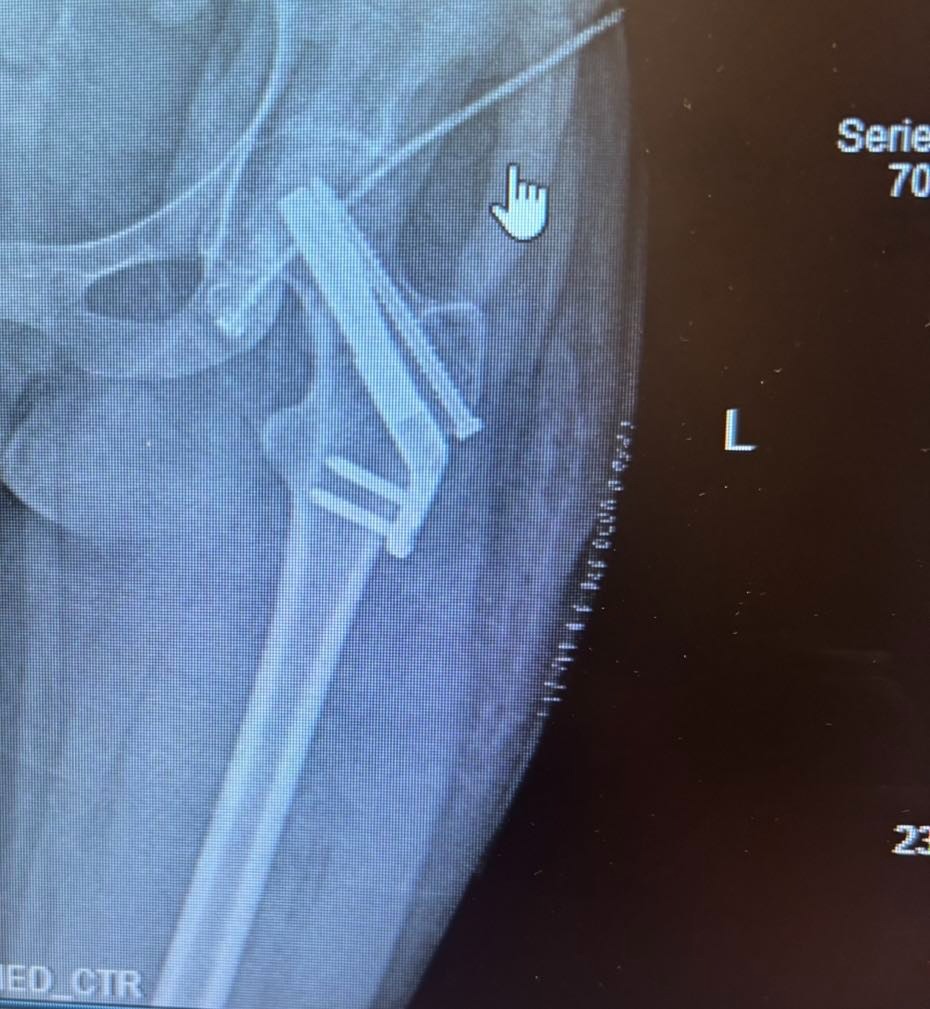

On Saturday, June 14th, 17-year-old Paisley Nicholl was a passenger in a tragic car accident that left her with serious injuries. Paisley suffered a broken humerus (upper arm) and a fractured hip, requiring a six-hour surgery to insert metal rods into both bones. The surgery took place at Northridge Hospital, but Paisley’s road to recovery is just beginning.